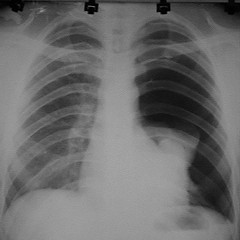

Click Imagen Ampliada

Fig. Masculino. 50 años.  APP: Fumador inveterado. MC: dolor torácico derecho intenso. Neumotórax derecho. RX: Colapso pulmonar de un 60%. Pequeño hemotórax que b0rra el seno costo-frénico derecho.